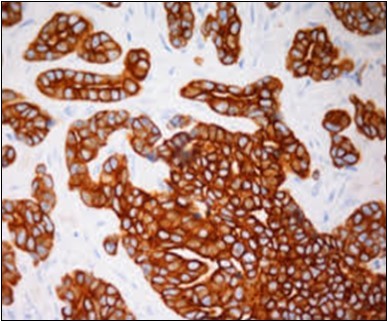

Figure 12.Immune reactivity to cyto-keratin (CK7) in eccrine porocarcinoma(24).

Eccrine porocarcinoma is immune reactive to carcino-embryonic antigen (CEA) and cyto-keratins 6 and 7(CK6,7), epithelial membrane antigen (EMA) and non reactive to S-100 protein. Reactivity to cyto-keratin 20 (CK20) assists the diagnosis in instances with indeterminate histology. Immune reactive p63, CK5 , weak P40 and non reactive GATA3 are additionally elucidated by the tumour 2, 3, 4.